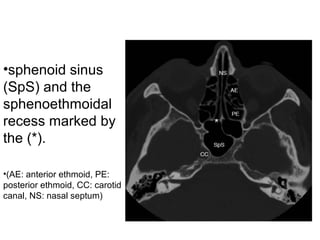

•sphenoid sinus

(SpS) and the

sphenoethmoidal

recess marked by

the (*).

•(AE: anterior ethmoid, PE:

posterior ethmoid, CC: carotid

canal, NS: nasal septum)

•sphenoid sinus (SpS) andthe sphenoethmoidal recess marked by the (*). •(AE: anterior ethmoid, PE: posterior ethmoid, CC: carotid canal, NS: nasal septum)